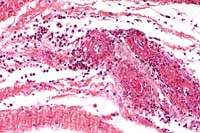

- Case 5- 2. Lung. The pleura and interlobular

septa are markedly expanded by clear space (edema) and scattered

lymphocytes an plasma cells. A pleural arteriole has fibrinoid

degeneration and necrosis of its walls with infiltrating and

adjacent lymphocytes and plasma cells.

- 1. Lung: Vasculopathy, characterized by endothelial syncytia,

mural necrosis, fibrinoid change, subacute perivasculitis, and

moderate interstitial edema, breed unspecified, equine.

- 2. Kidney, interstitial and glomerular blood vessels: Vasculopathy,

characterized by endothelial syncytia, mural necrosis, and fibrinoid

change.

- Conference Note: In some sections of lung and kidney,

rare eosinophilic intracytoplasmic inclusions are present within

endothelial syncytia. Mild degenerative changes of glomeruli

and tubular dilatation were also noted by some conference participants.